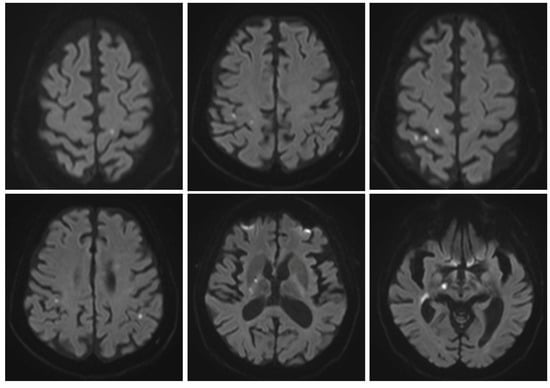

The first cerebral ischemic event manifested as left hemiparesis that occurred one year later (in 2018). No recognizable etiology of the ischemic stroke was found, and an insertable cardiac monitoring device was implanted. Starting two years after this first cerebral event, the patient slowly developed a progressive decrease in visual acuity and severe physical and cognitive deterioration. He underwent multiple brain magnetic resonance images (MRIs), which showed an accumulation of (sub)acute lacunar brain infarction, i.e., small (<20 mm in diameter) ischemic lesions that affect the CNS white and grey matter, as well as diffuse brain and optic nerve atrophy (Figure 2). Several serological screening tests for common infections, rheumatologic/systemic vasculitis, and inherited or acquired coagulation disorders were negative over time, except for an isolated lupus anticoagulant (LAC) positivity, which was not confirmed after at least 12 weeks. Carotid and transcranial doppler ultrasounds, MR angiography, and cardiac electronic devices–remote interrogations were steadily unremarkable. During the hospitalization at our clinic in 2022, CSF analysis showed an increased level of protein (71.3 mg/dL-n.v.: 15.0–45.0 mg/dL) and intrathecal oligoclonal bands (OCBs), together with its analogous presence in the peripheral blood (pattern type 4—“mirror”). Neither leukocytes nor red blood cells nor increased lactate levels were present in the CSF. Testing for antibodies for paraneoplastic syndrome was negative. At the same time, the CSF multiplex–polymerase chain reaction assay ruled out neuroinfectious diseases, and CNS intravascular neoplasms appeared unlikely since radiological evaluation, CSF cytopathology and flow cytofluorimetry were both negative, and the disease course was not rapidly progressive. Visually evoked potentials (VEPs) showed bilateral abnormalities, which were worse on the right side, mainly due to axonal damage (Figure 3), and a fundoscopic inspection did not demonstrate pathologic findings. Optical coherence tomography and fundus fluorescein angiography were not performed. No strategic infarct at the visual cortex was evident on brain MRI. Nerve conduction studies showed normal conduction velocities, latency, and amplitudes in the limbs’ main motor and sensory nerves; a needle electromyography was within limits.

Figure 2. Exemplification of the evolution of brain ischemic damage over time. Axial fluid-attenuated inversion recovery (FLAIR) MRI images showing the progressive accumulation of subcortical microinfarcts associated with the development of cortical–subcortical brain atrophy. Top row (2018), middle row (2022), bottom row (2023).

Based on these data, ischemic immune-mediated cerebral and optic nerve complications of HSCT as possible manifestations of cGVHD were suspected. Therefore, the patient was placed on immunosuppressive treatment with steroids (1 mg/kg/day prednisone). Unfortunately, after almost a year of treatment without worsening of the neurological status, the steroid dosage was slowly tapered over eight weeks due to the occurrence of adverse effects (mood swings, fluid retention, elevated blood pressure, dermatitis, and ecchymosis), with a subsequent flare-up of neurological symptoms (dysphagia, dysarthria, worsening of left hemiparesis, challenges with visual perception, confusion, and disorientation in familiar places) and MRI evidence of new cerebral acute ischemic foci, causing a worsening of the patient’s neurological status (Figure 4) three months after stopping the steroid treatment. At the end of 2023, after a reprised laboratory-instrumental diagnostic work-up, including a second CSF analysis confirming only an increased level of protein (84 mg/dL) in the absence of pleocytosis (0, 000 10*3/uL leukocytes), the patient’s care target was directed to comfort measures until his death a year later. Remarkably, during the overall follow-up, the patient showed no cutaneous and visceral manifestations of cGVHD or evidence of systemic thrombus formation. Post-transplant immune-mediated thrombotic microangiopathy/angiitis involving brain parenchyma and optic nerves could better explain the clinical picture as a conceivable presentation of isolated CNS involvement of cGVHD.